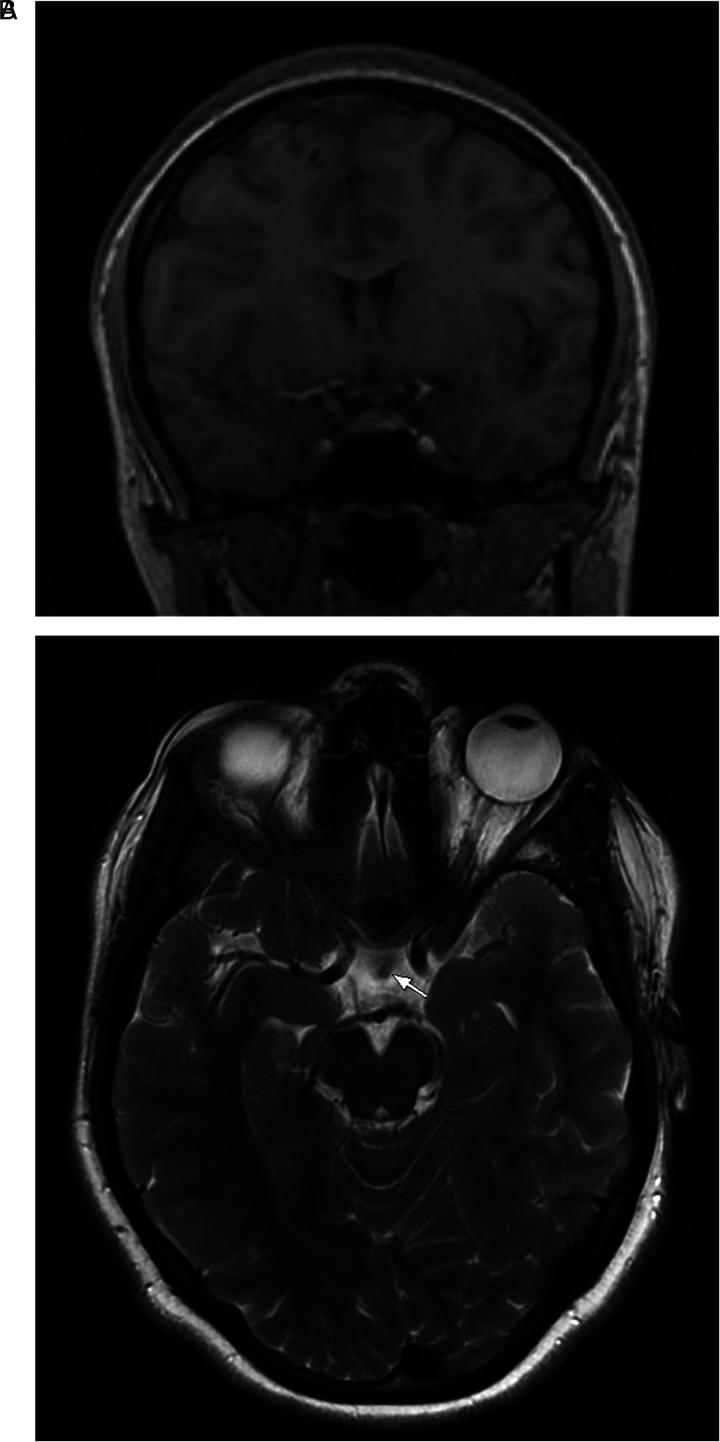

Lymphocytic hypophysitis (LH) is a rare autoimmune disorder involving the destruction of the anterior pituitary due to lymphocytic infiltration. The disease shows a female predominance, commonly affecting women during late pregnancy into the postpartum period. The etiology of LH has not been well established and is presumed to be autoimmune based on the histopathological findings of lymphocytic infiltration and postpartum cases. Lymphocytic hypophysitis has yet to be studied in the context of a patient status post-recovery from COVID-19. Since the initial outbreak, additional information regarding the symptoms and outcomes has emerged on the virus's effects on the nervous system. We present a novel case of post-COVID lymphocytic hypophysitis in a pediatric patient at Dayton Children's Hospital. An 18-year-old previously healthy girl presented to the emergency department (ED) with acute onset headache and dizziness for 5 days. She had a history of symptomatic COVID-19 three weeks prior to the onset of current symptoms. Contrast enhanced magnetic resonance imaging (MRI) of the brain revealed diffuse thickening and enlargement of the infundibulum with homogenous contrast enhancement of the hypophyseal axis. Based on the suspicion for lymphocytic hypophysitis, she was started on Methylprednisolone 250 mg IV Q6hrs on day 1-3. Symptomatic clinical improvement was seen on day 3 with a significant decrease in the intensity of the headache. The case illustrates the varied presentation and neurological sequalae associated with the COVID-19 virus. The case described here is the first ever reported post-COVID manifestation of lymphocytic hypophysitis.

淋巴细胞性垂体炎(LH)是一种罕见的自身免疫性疾病,由于淋巴细胞浸润导致腺垂体破坏。该病以女性为主,常见于妊娠晚期至产后的女性。LH的病因尚未完全明确,基于淋巴细胞浸润的组织病理学发现及产后病例推测其为自身免疫性疾病。淋巴细胞性垂体炎在新冠病毒感染康复后的患者情况中尚未得到研究。自最初爆发以来,关于该病毒对神经系统影响的症状和后果出现了更多信息。我们报告了代顿儿童医院一名儿科患者的新冠后淋巴细胞性垂体炎新病例。一名18岁既往健康的女孩因急性发作头痛和头晕5天就诊于急诊科。在当前症状出现前三周,她有症状性新冠病毒感染病史。脑部增强磁共振成像(MRI)显示漏斗弥漫性增厚和增大,垂体轴均匀强化。基于对淋巴细胞性垂体炎的怀疑,在第1 - 3天给予她静脉注射甲泼尼龙250mg,每6小时一次。第3天症状出现临床改善,头痛强度显著降低。该病例说明了与新冠病毒相关的多样表现和神经后遗症。此处描述的病例是首次报道的新冠后淋巴细胞性垂体炎表现。